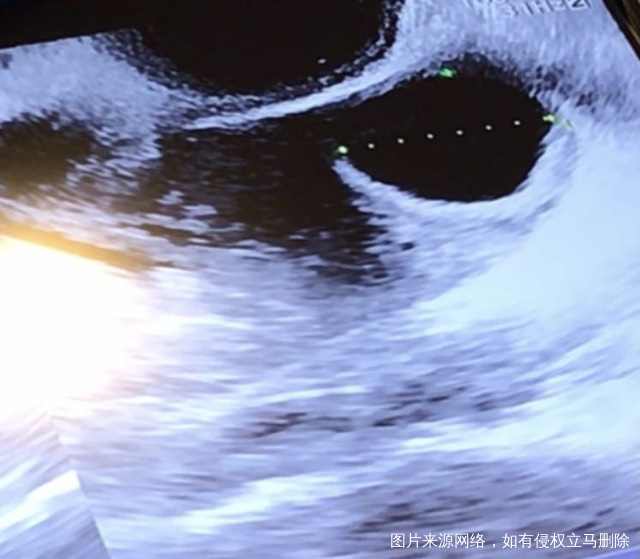

第一张图排卵前卵泡20毫米第二张图排卵后第六